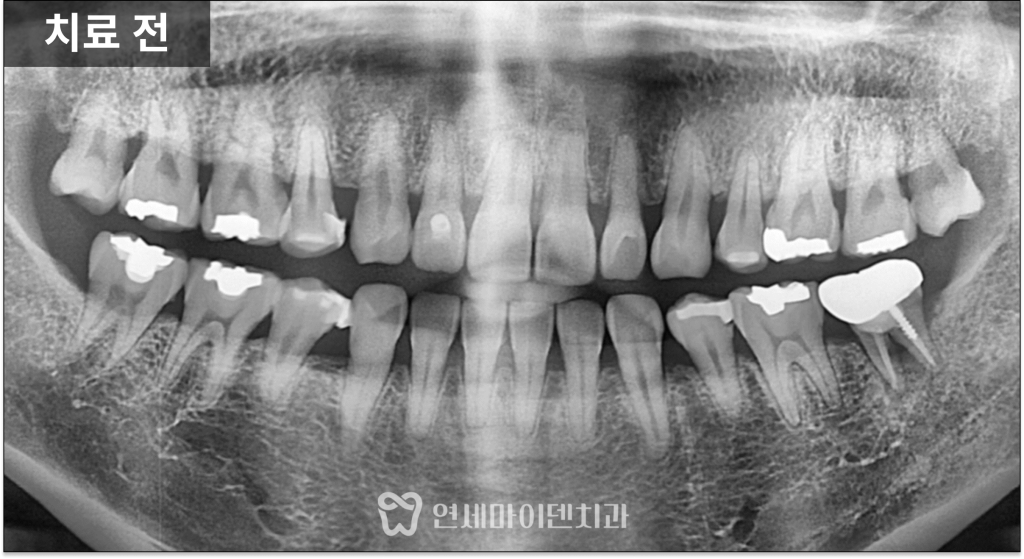

과거 신경치료 후 발생한 문제

문제가 된 치아는

과거 신경치료 후 금니로 수복되어 있었고,

잇몸에는 고름이 배출되는

이른바 ‘잇몸 여드름’이 관찰되었습니다.

발치 여부를 결정한 핵심 기준

하지만 이 케이스에서는

치아 뿌리가 갈라지는 부위인

분지부까지 뼈가 녹아 있는 상태였습니다.

분지부 뼈가 손상되었다는 것은

치아를 지지하는 구조 자체가

무너졌다는 의미입니다.

여기에 더해

치아의 흔들림도 심하게 동반되어 있었고,

장기적으로 안정적인 유지가 어렵다고 판단되어

발치를 선택할 수밖에 없었습니다.